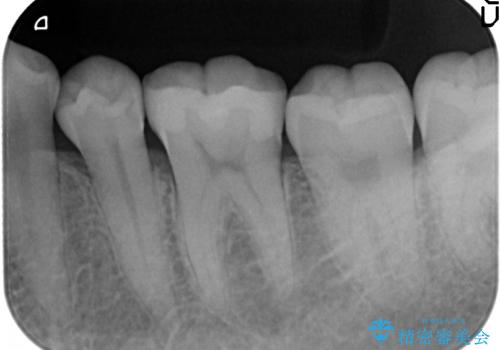

マイクロスコープを用いることで歯の微細な硬さや虫歯の広がりをすみずみまで精査することができます。

しっかりと虫歯を取り除き、精密なインレーを装着することで虫歯の再発を防ぎ長期的な予後を期待できる環境を整えます。